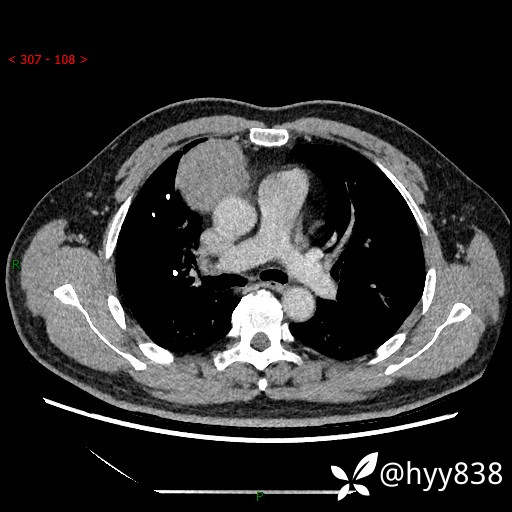

胸部CT平扫